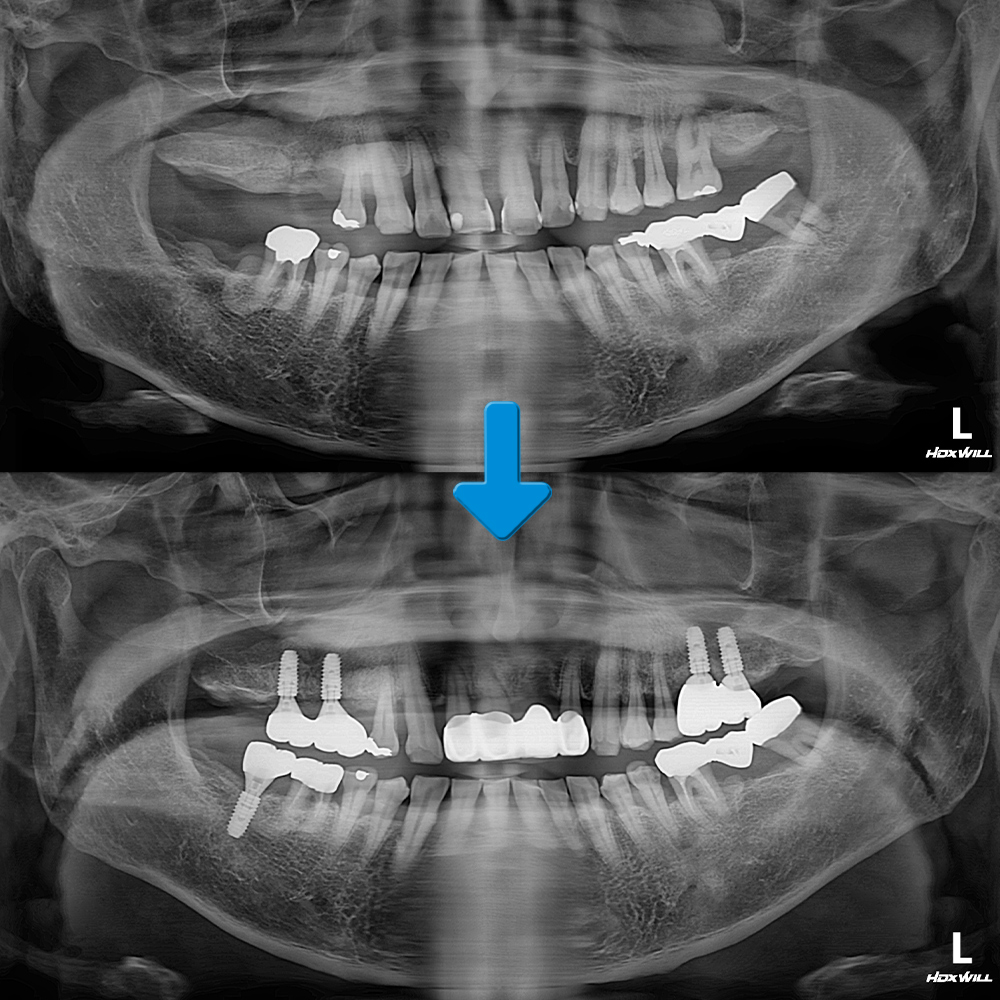

오늘은 가정동치과에서 양쪽 위 어금니 부위 상악동 거상술을 동반한 임플란트 식립과 앞니 브릿지를 진행하신 환자분을 소개해 드리도록 하겠습니다.

환자분께서는 오른쪽의 어금니는 상실하신지 오래 되셨고 남아 있는 왼쪽의 치아들도 흔들리며 좋지 않은 느낌이 드셔서 전체적인 치료를 위해 가정동치과에 내원해 주셨는데요. 심한 치주염으로 인해 잇몸뼈가 많이 녹아 있어 남아 있는 왼쪽 위 어금니도 좋지 않은 상태였고 뻐드러지고 벌어져 있는 앞니도 함께 치료를 권유드렸습니다. 따라서 양쪽 위 흡수된 잇몸뼈는 상악동 거상술을 통해 많은 양의 뼈이식과 더불어 임플란트 식립 및 앞니 브릿지를 진행하시기로 하였습니다.

어금니 임플란트와 앞니 보철까지 마무리한 모습입니다.